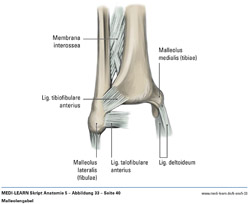

• Malleolengabel